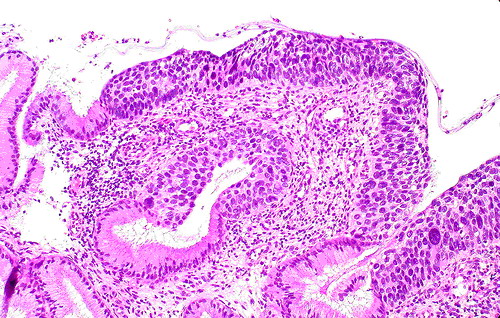

举例来说,慢性宫颈炎(宫颈糜烂)与宫颈癌在妇科阴道镜检查时观察到的表现可以相似。行宫颈刮片的细胞检查时看到的也可以相似(图1、2)。最后采取组织行病理切片检查,也是有相似之处,不是容易做出100%鉴别的(图3、4)。这样看来,如果仅一次检查(或一家医院检查),就肯定是癌,而行手术切除,是不慎重的,错误率是高的。最好是如果要手术切除,应到第二家医院或第二个医生核实后进行下一步治疗。

图3 宫颈炎看到的切片

图4 宫颈癌时看到的切片